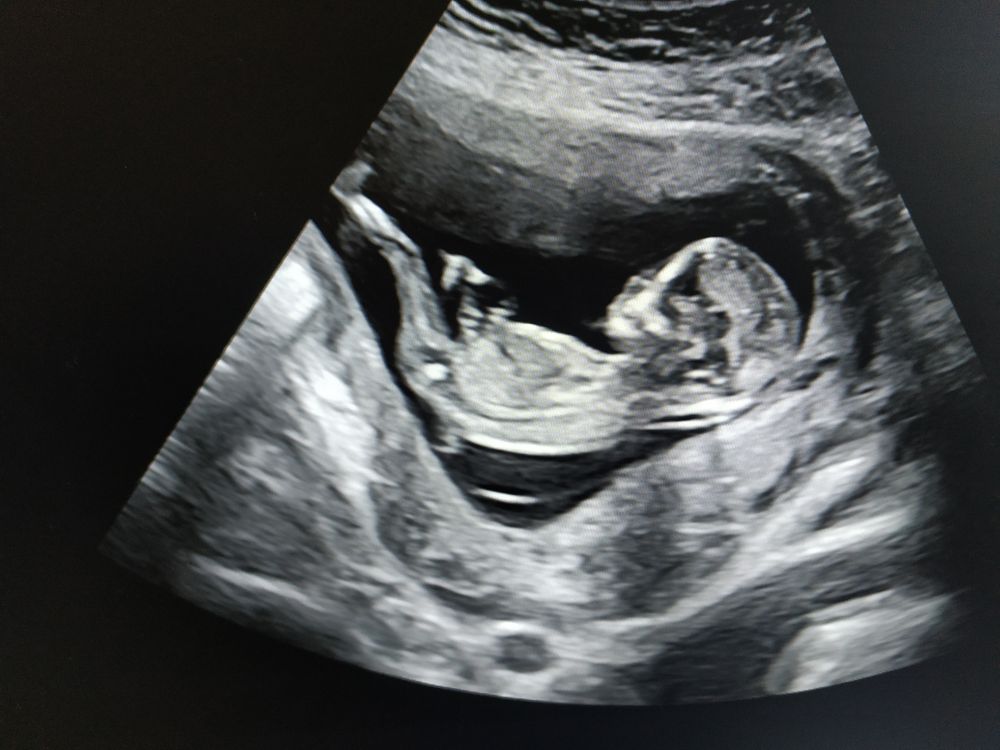

Была на первом скрининге (у Тимм, как и в прошлый раз)). Смотрела как и тогда молча, сказала только, что малыш на 13 недель и 6 дней (а по месячным сегодня ровно 13), и поставила пдр на 16 мая. Со старшим сыном она ставила на 19 марта, родился 21)

На снимке малыш длинноногий, наверное, будет таким же высоким, как старший брат)) а профиль на старшего совсем не похож, так интересно! Я раньше думала, что на УЗИ все малыши примерно одинаково выглядят, а нет, уже видно, что внешность другая)

А малыш и правда длинноногий у вас. Во всей красе разлегся))))

Классная фотка 😄 будто нога на ногу лежит. На чиле, на расслабоне 🤣🤣🤣👍🏽👍🏽👍🏽

Как время летит, я в прошлом году тоже беременной ходила, пдр на 12 мая ставили, родила 1 числа. Он у вас прям как будто лежит, загорает:) И по УЗИ они оказывается все разные - сравнила снимки двух сыночек, не похожи. Когда младший родился - совершенно другой - светлый, сероглазый, форма глаз, губ другая. А старший у меня смуглый, с карими глазами)))